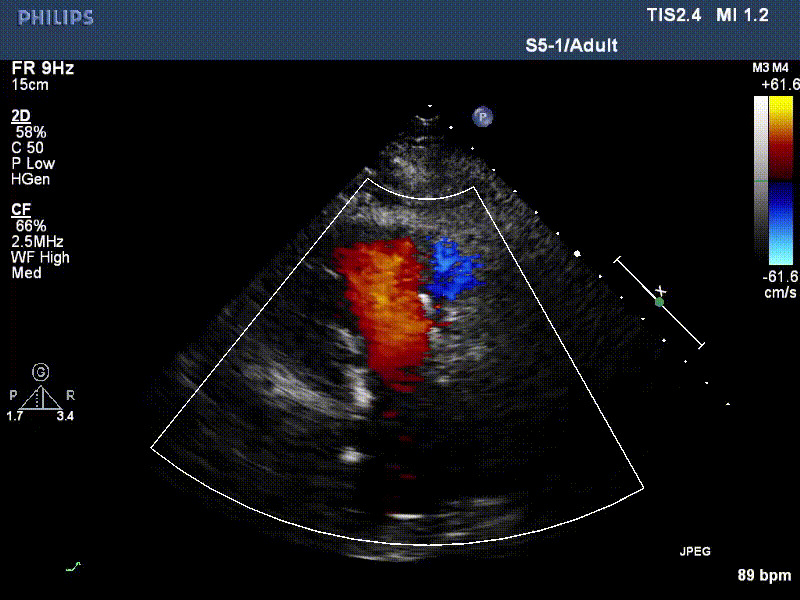

流并分別伴有房顫和房撲,高外科手術(shù)風險。術(shù)前超聲提示,兩例患者下腔靜脈寬度分別為13mm和29mm,右房內(nèi)徑(上下徑和左右徑)分別為52×41mm和53×43mm,彩色多普勒顯示極重度三尖瓣反流,VCW分別為14×15mm和10mm。

1年前,兩例患者因難治性雙下肢水腫輾轉(zhuǎn)多家醫(yī)院尋求救治,考慮到兩例患者高齡、基礎疾病多、STS評分高,不適合傳統(tǒng)外科開胸手術(shù),葛均波院士及其團隊周達新教授、潘文志教授、張源博士、陳莎莎博士、陳丹丹博士聯(lián)合心外科王春生、魏來主任,麻醉科繆長虹、郭克芳主任以及心超室的潘翠珍教授、李偉教授共同討論決定,采用我國創(chuàng)新器械LuX-Valve Plus經(jīng)血管三尖瓣置換系統(tǒng)為患者進行手術(shù)。相較于第一代產(chǎn)品LuX-Valve,LuX-Valve Plus經(jīng)血管三尖瓣置換系統(tǒng)對輸送系統(tǒng)進行了全面升級,實現(xiàn)了經(jīng)頸靜脈入路的方式,進一步減小了手術(shù)風險和對患者的創(chuàng)傷。目前隨訪1年心超結(jié)果顯示,三尖瓣極重度反流消失,人工三尖瓣瓣膜穩(wěn)定牢固,瓣葉活動度良好,右心室及下腔靜脈明顯縮小,心輸出量增加。兩位老人手術(shù)后沒有出現(xiàn)過胸悶氣促的癥狀,下肢水腫緩解,活動耐力提升,生活質(zhì)量也大為提高。

圖2 患者植入LuX-Valve Plus后,1年隨訪心超提示無三尖瓣反流